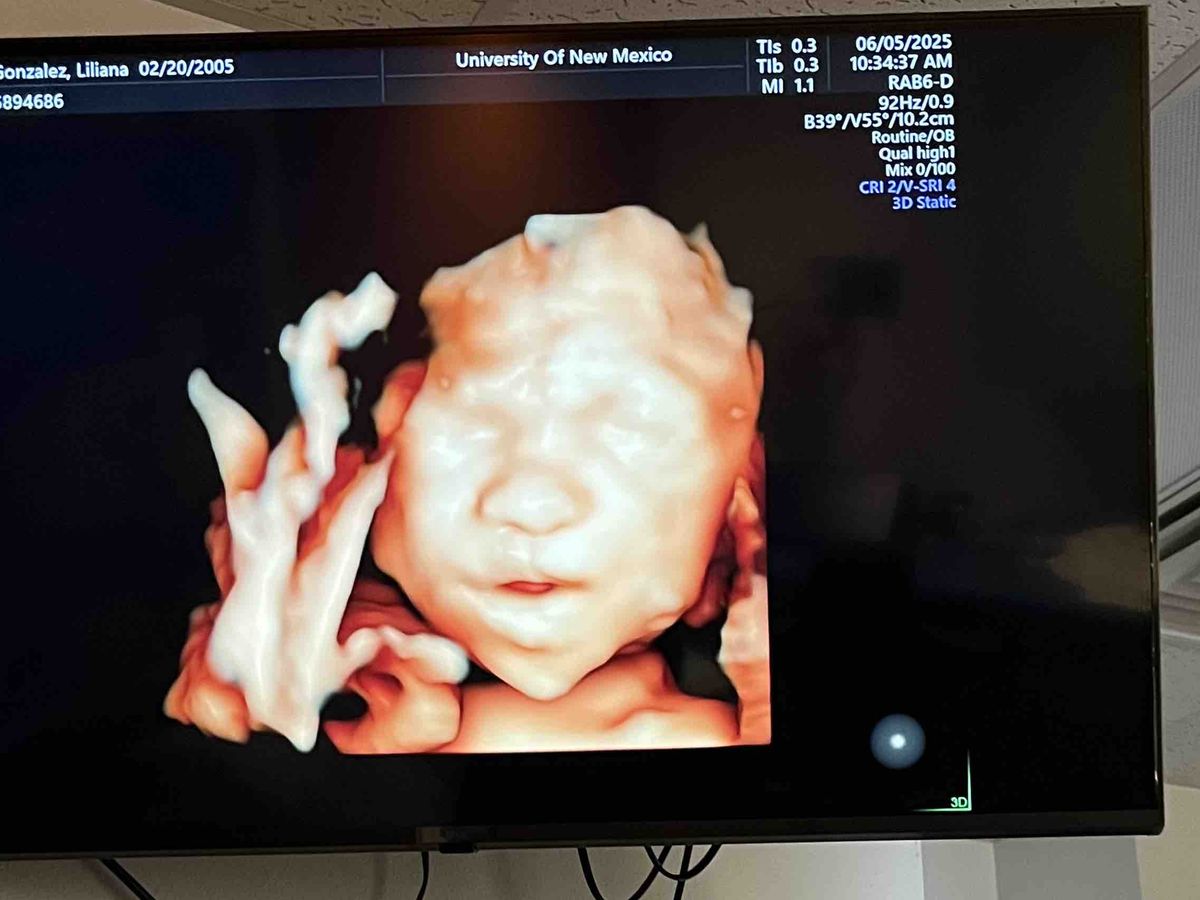

Hi my name is Lilliana Gonzalez I’m 25 weeks pregnant and I’m having to make travel plans to Denver, Colorado or California for my unborn baby he has a heart defect called pulmonary atresia

and I’m having to travel to a specialist and I’m trying to raise money to help get us there. Anything is gladly appreciated!